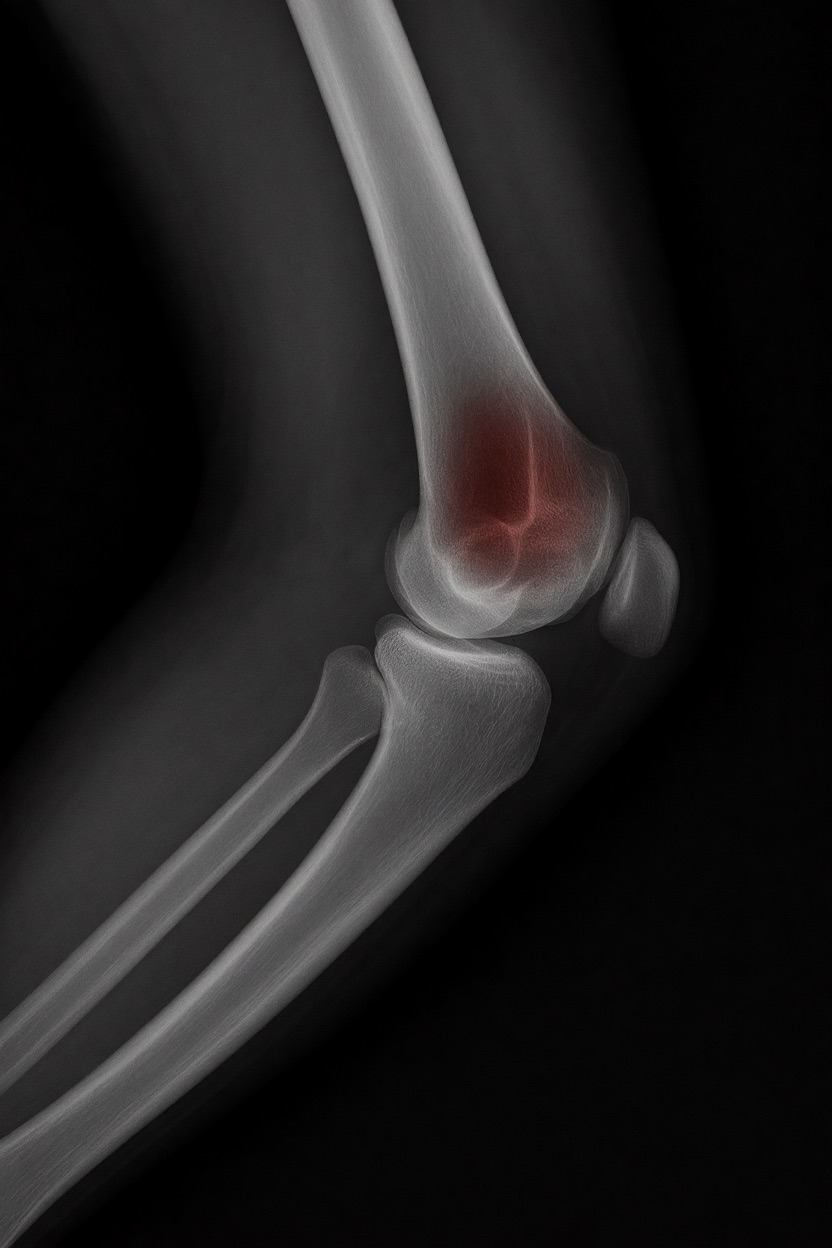

不適切な用途

- 重大な診断には使用しない

- 医師の代わりにはならない、まったくもって!

重要

このLoRaは視覚的実験用のみです。

医療機器ではありません。信頼性がなく、臨床診断には使用しないでください。

もちろん、このツールはオープンソースで、高速(1回の分析に25秒)、一般のデスクトップPCで動作するため、今後このコンセプトをさらに実験する価値はあると思います…今後の展開に注目です!